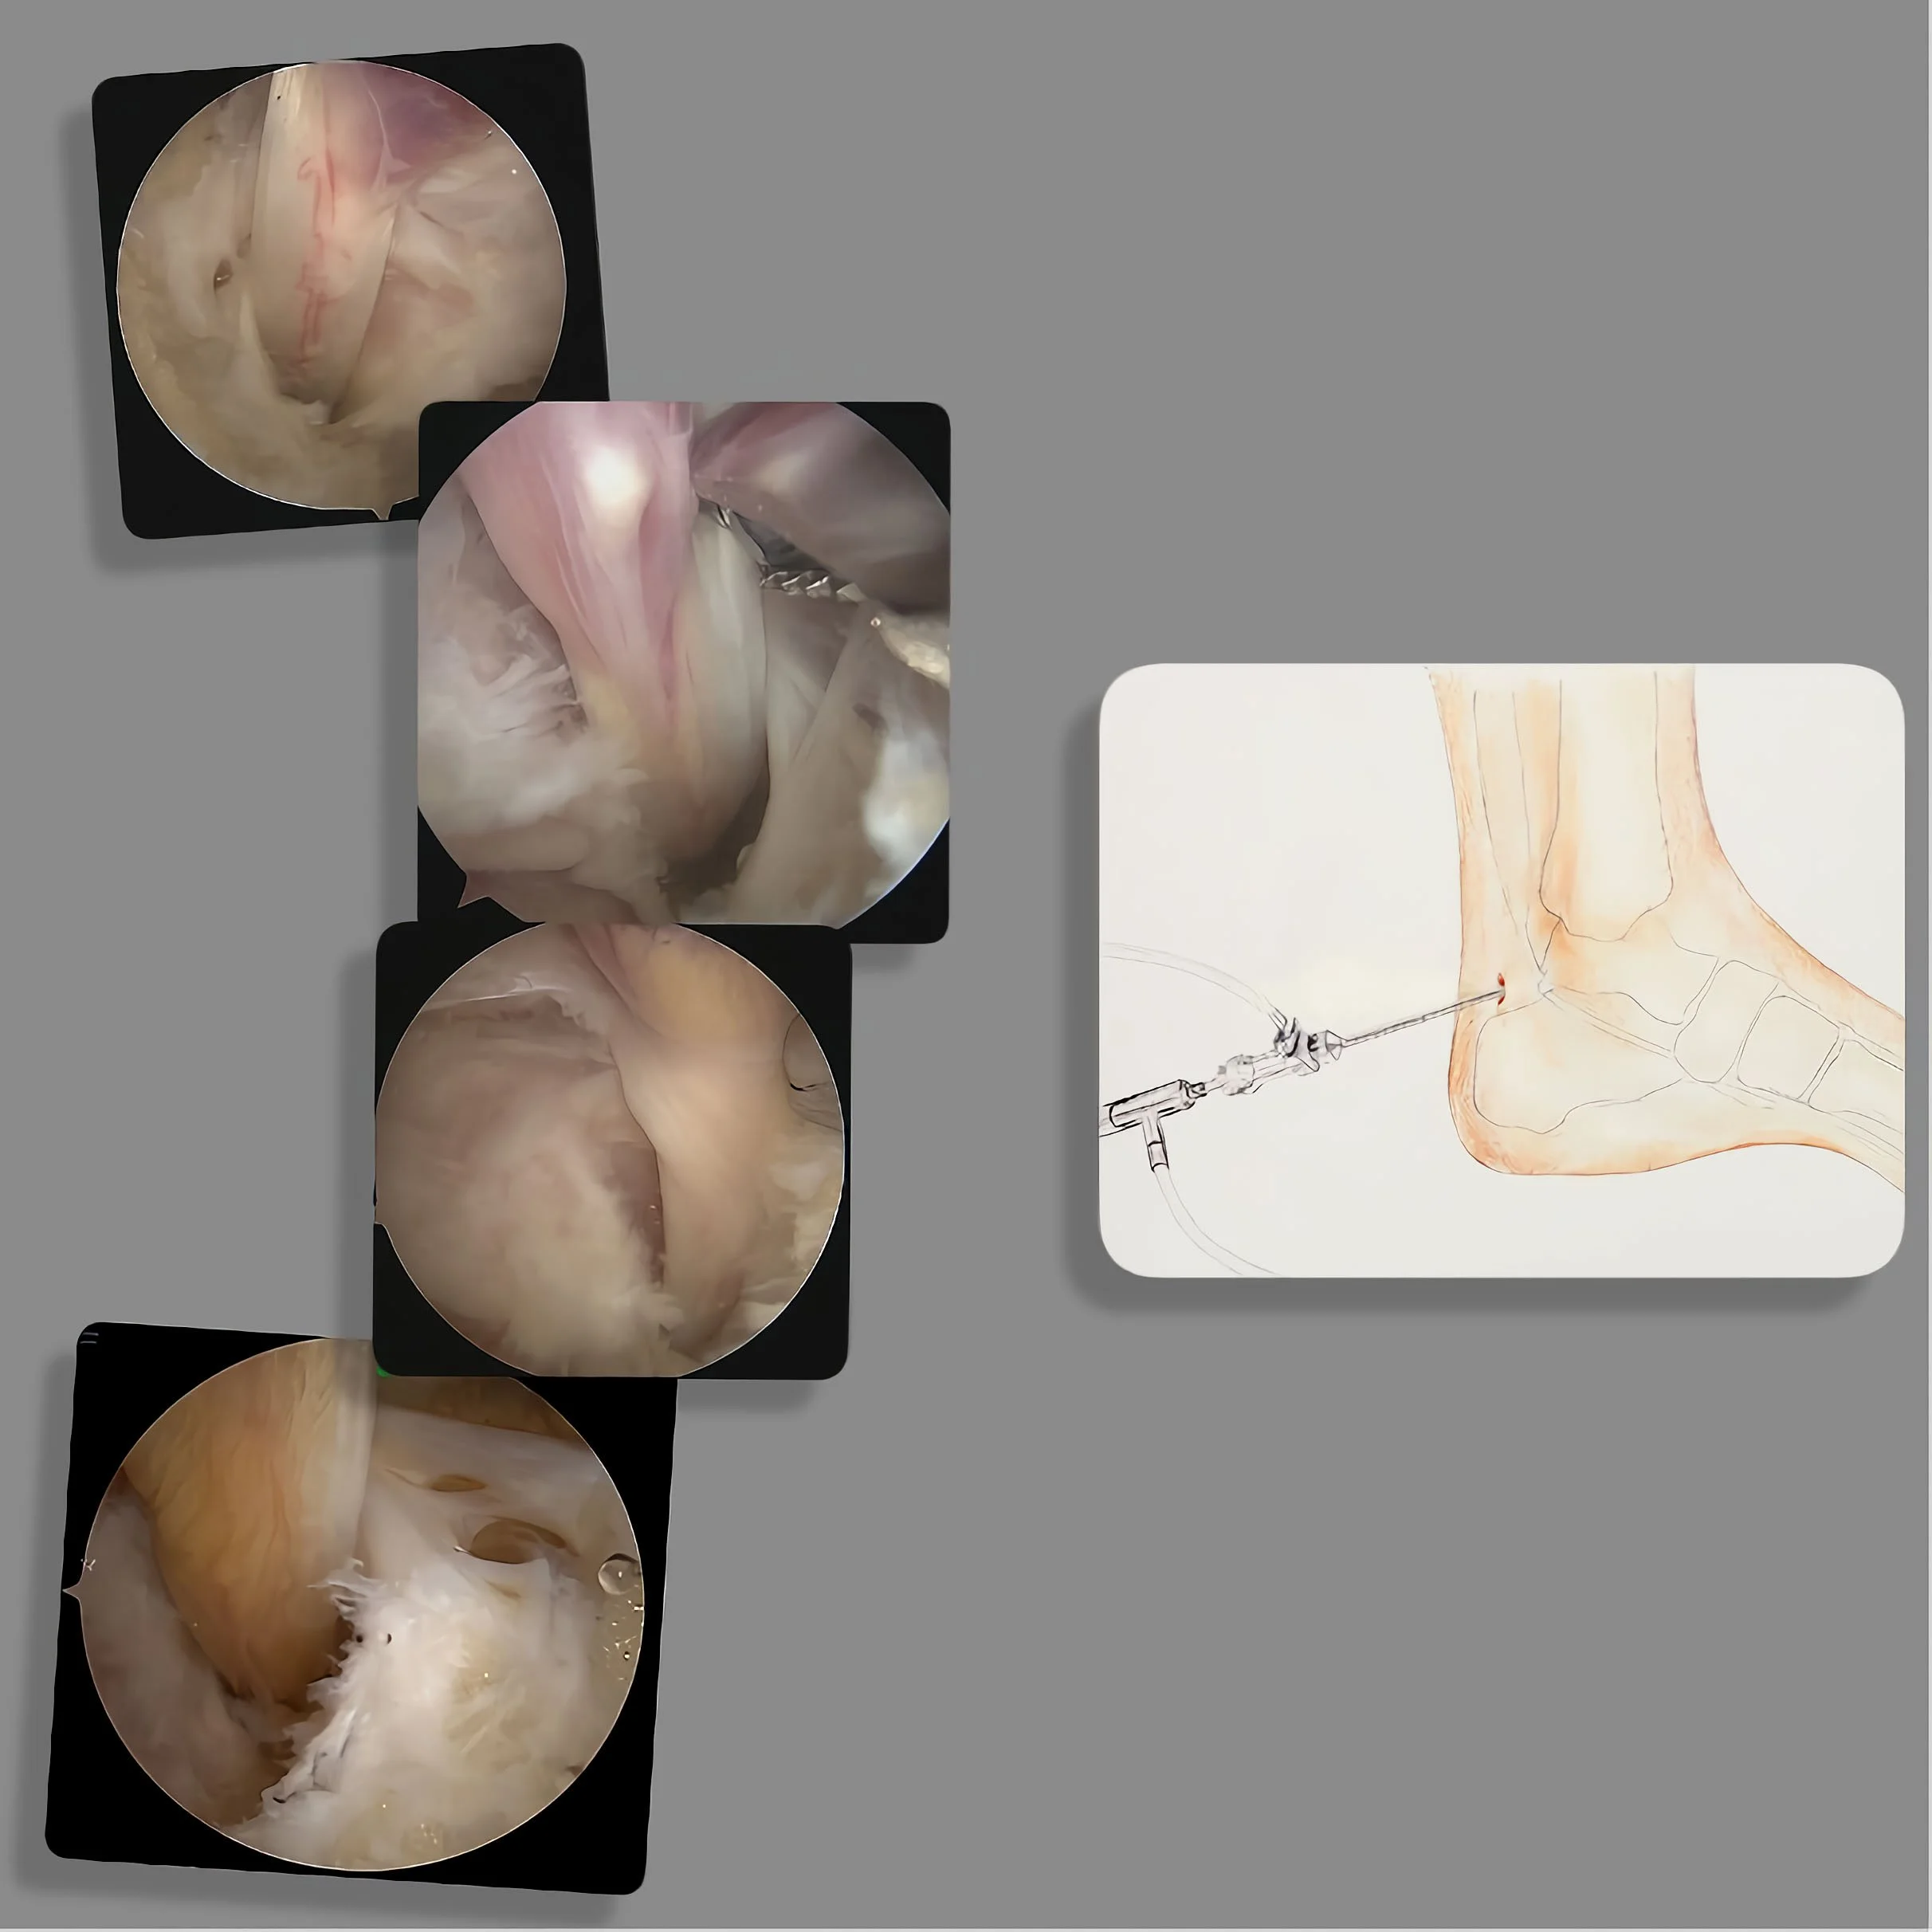

De operatieve behandeling van de lange buiger van de grote teen kan met een kijkoperatie techniek:

De naam kijkoperatie is soms wat misleidend, wij noemen het een kijkoperatie omdat er door middel van een camera en een beeldscherm wordt geopereerd. Maar het is niet alleen kijken, er wordt ook wat gedaan!

In het Engels wordt de kijkoperatie ‘key hole surgery’ genoemd en dit dekt veel meer de lading van de operatie. Bij de enkel maken wij gebruik van een kijker (de arthroscoop) en speciale instrumenten. Hierdoor kan door 2 kleine gaatjes van vaak minder dan 1 cm de operatie worden uitgevoerd.

De kijkoperatie vindt aan de achterzijde van de enkel plaats u moet op uw buik liggen voor deze operatie!

De sneetjes van ongeveer 5 mm worden net naast de achillespees gemaakt. Via het ene sneetje wordt de camera naar binnengebracht en via het andere sneetje de instrumenten. Nu kan via een scherm de operatie worden uitgevoerd. Vaak wordt gebruik gemaakt van verschillende instrumenten.

Bij de operatie aan de achterzijde van de enkel, moet er altijd eerst weefsel worden verwijderd, omdat de operatie niet direct in het gewricht begint. Het meeste wordt gedaan aan de achterzijde van het bovenste spronggewricht. Natuurlijk wordt ook het enkelgewricht bekeken en zo nodig schoongemaakt. Omdat er meer weefsel verwijderd zal moeten worden in vergelijking met bijvoorbeeld een kijkoperatie van de voorzijde van de enkel of van de knie, is de enkel na de operatie nog lang dik.